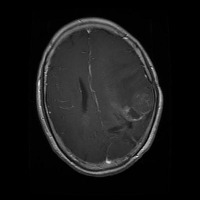

This project has created a labeled MRI brain tumor dataset for the detection of three tumor types: pituitary, meningioma, and glioma. The dataset contains 2443 total images, which have been split into training, validation, and test sets. The training set has 1695 images, the validation set has 502 images, and the test set has 246 images.

- Image types: MRI scans

Classes:

- Pituitary tumor

- Meningioma tumor

- Glioma tumor

- No Tumor

- The images have been labeled by medical experts using a standardized labeling protocol.

- The labels include the type of tumor and the location of the tumor.